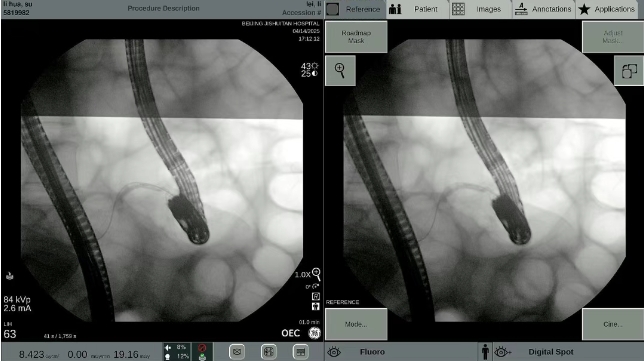

X线下查看阑尾腔支架的形态和位置

术中造影可见阑尾内多发充盈缺损